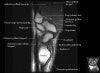

- Sagittal section

Sagittal T1 evaluates the tendons, bone marrow and relationships between the osseous structures.